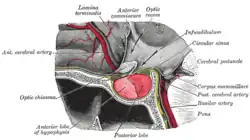

Die Adenohypophyse (griechisch-lateinisch: Adenohypophysis) ist der drüsige (endokrine) und größere Teil der an der Basis des Gehirns liegenden Hirnanhangsdrüse (Hypophyse) und besteht aus dem Hypophysenvorderlappen und dem Hypophysenmittellappen oder Hypophysenzwischenlappen.[1] Häufig wird „Adenohypophyse“ auch synonym mit „Hypophysenvorderlappen“ verwendet.[2] Die Adenohypophyse produziert, gesteuert von Hormonen des Hypothalamus, das Wachstumshormon sowie andere Drüsen (Schilddrüse, Keimdrüsen, Nebennierenrinde) kontrollierende Hormone. Sie geht entwicklungsgeschichtlich aus der Rathke-Tasche der Mundbucht hervor und wird somit oft nicht als ein Teil des Gehirns erachtet, im Gegensatz zur Neurohypophyse. Während der Hypophysenvorderlappen beim Menschen (und auch Paarhufern) den vorderen Teil der Hypophyse darstellt, umgibt er bei einigen Säugetieren (z. B. Raubtieren und Pferden) die Neurohypophyse (Hypophysenhinterlappen) vollständig.

Die Adenohypophyse besteht aus drei Teilen:

- Der Vorderlappen (die Pars distalis) ist der vorderste Teil der Hypophyse. Er enthält azidophile Alpha-, basophile Beta-, chromophobe Gamma- und azidophile Etazellen (= Schwangerschaftszellen).

- Der Zwischenlappen (die Pars intermedia) befindet sich zwischen Vorderlappen und Hinterlappen (Teil der Neurohypophyse). In seinen Zellen wird Melanozyten-stimulierendes Hormon (MSH) gebildet.

- Der Trichterlappen (die Pars tuberalis) umgreift von vorne den Hypophysenstiel (Teil der Neurohypophyse). Über seine Funktion ist bislang nichts bekannt.